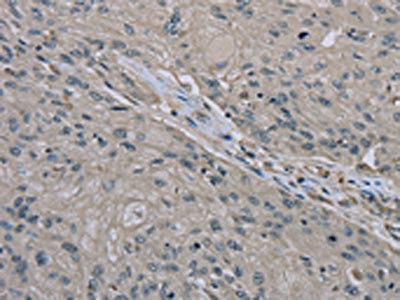

The image on the left is immunohistochemistry of paraffin-embedded Human thyroid cancer tissue using CSB-PA198612(EDN1 Antibody) at dilution 1/30, on the right is treated with fusion protein. (Original magnification: ×200)

The image on the left is immunohistochemistry of paraffin-embedded Human esophagus cancer tissue using CSB-PA198612(EDN1 Antibody) at dilution 1/30, on the right is treated with fusion protein. (Original magnification: ×200)